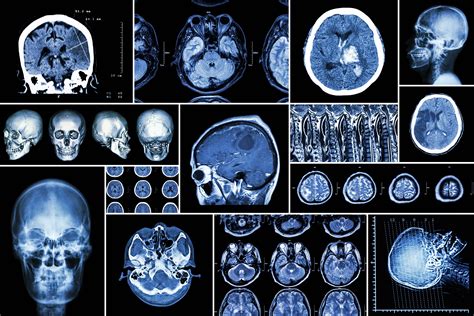

医学影像学

医学影像学专业五年制国家级特色专业建设点招收理科授予本科毕业证书、医学学士学位培养目标及要求:培养德、智、体全面发展的从事医学影像诊断、介入放射学和医学成像技术等方面工作的医学高级专门人才。要求学生学习掌握现代医学方面的基础理论和基本知识,接受常规放射学等多方面的操作技能的基本训练,具有常见病的影像诊断和介入放射学操作基本能力。主要专业课程:以基础医学、临床医学、医学影像学为主干学科。主要课程有医用电子学、系统解剖学、生理学、生物化学与分子生物学、医学免疫学、病理学、诊断学、内科学、外科学、放射诊断学、CT诊断学、MR诊断学、介入放射学、核素诊断、超声诊断学、放射肿瘤学等。就业方向:毕业后在各级综合性医院、专科医院、肿瘤医院、医学院校和医学科研部门、医学影像设备厂家等单位,从事临床医学影像诊断、放射治疗和医学教育科研等工作。